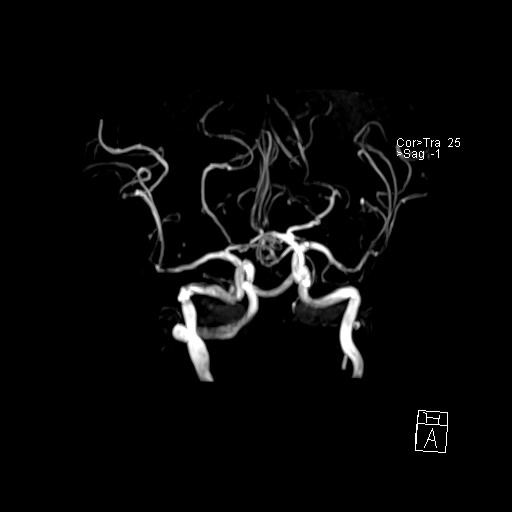

239716 - VILLANUEVA, WILLIAM A. - Number 3 |

|

239716 - VILLANUEVA, WILLIAM A. - Number 3 |